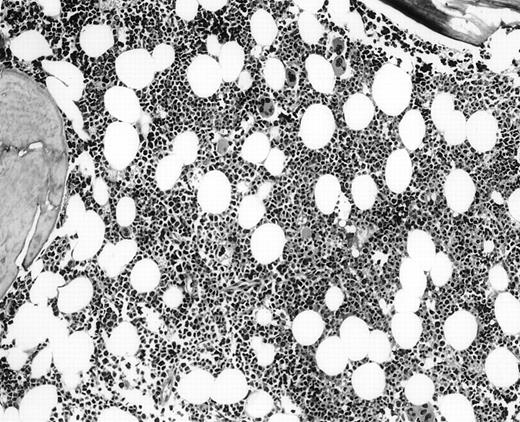

The 5 BM morphology-negative, flow cytometric-positive cases were all from patients with large-cell lymphomas (Table 3). Four patients, independent of the flow results, had localized, but bulky clinical disease: 1 with stage I, 2 with stage II, 1 with stage III, and 1 with widespread stage IV disease. All were treated with chemotherapy, independent of knowing the positive flow cytometric immunophenotyping results. No morphologic or immunohistochemical evidence of lymphoma was seen in these 5 BM biopsy specimens (Fig2). Substantial bilateral biopsy material was available, ranging from 2 to 6.5 cm of trephine biopsy. Interestingly, the PB contained the same B-cell clone in 2 of 2 cases in which concomitant blood immunophenotyping was also performed. These 5 cases showed small monoclonal populations by flow cytometric analysis that ranged from 0.09% to 3% of the overall cell population analyzed, indicating that all cases had an extremely small population of clonal cells. Unfortunately, insufficient follow-up time has accrued that would allow clinical outcome analysis in this interesting subset of patients.

BM biopsy showing a normocellular marrow with no morphologic features of lymphoma, confirmed by negative immunohistochemical staining. A lymph node biopsy showed a large-cell lymphoma. Flow cytometric studies of the marrow aspirate demonstrated a small population of monoclonal B cells (H&E; original magnification × 400).